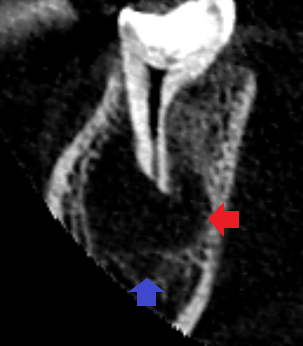

下顎第二大臼歯の初診時の矢状断のCT画像です。

赤い矢印の先に大きな膿の影がみられます。青い矢印の先にみられる下顎管という太い神経の通り道に膿の影が接しており、膿が神経を圧迫して激痛を発していることが考えられました。